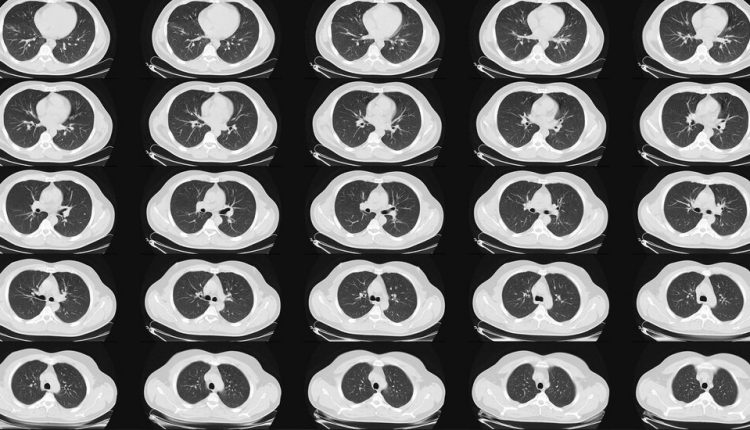

Lung Most cancers Scans Are Advisable for Folks 50 and Older With Shorter Smoking Histories

“There is evidence that a fairly simple, five-minute, low-dose, low-radiation scan can really save many lives,” said Dr. Bernard J. Park, pulmonary surgeon and clinical director of the lungs. Screening service at the Memorial Sloan Kettering Cancer Center in New York. Around 75 to 85 percent of the cancers found in this screening are in stage 1 and it is estimated that only surgery or radiation can be cured.